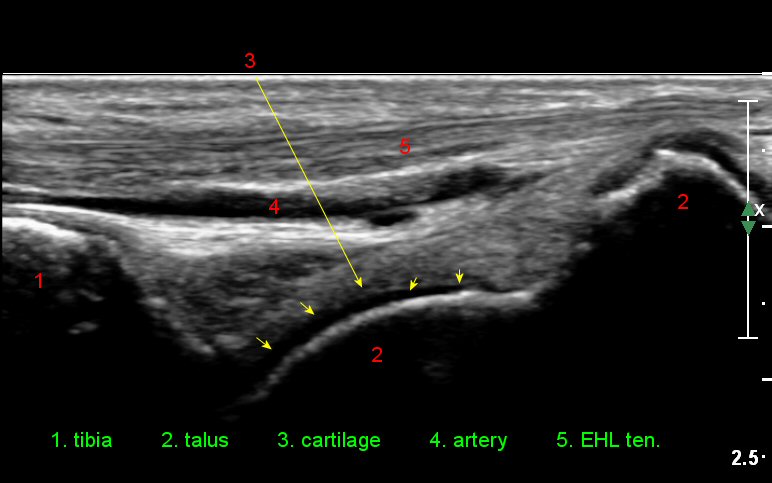

¹ß¸ñ°üÀý ¾ÕÂÊ Á¾´Ü¸é°Ë»ç¿¡¼­ ƯÀÌ ¼Ò°ßÀ» º¸ÀÌÁö ¾ÊÀ¸³ª(»çÁø 1)

ŽÃËÀÚ¸¦ ÀÎÁ¢ÇÑ ºÎÀ§·Î À̵¿ÇÏ´Ï ¼Ò·®ÀÇ °üÀý³» ¼ö¾×Àú·ù°¡ °üÂûµÈ´Ù(»çÁö 2).